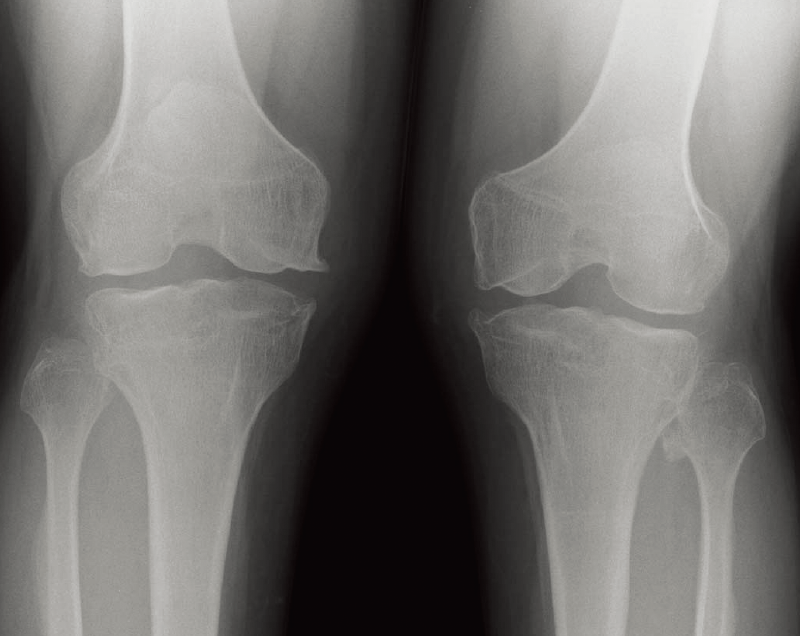

B. 両膝正面像(21歳、男、Kozlowski型):関節の腫大と関節面の不整を認める。

長管骨骨幹端部は広がり(flaring)、関節面の不整を認める(B)。

特徴的な画像所見:扁平椎の程度は強く、前後径、左右径ともに増大する(A)。

ムコ多糖症と鑑別する上で重要な診断のポイント

関節拘縮と体型が類似する。正常顔貌で眼や耳の合併症が少ない点がムコ多糖症とは異なる。